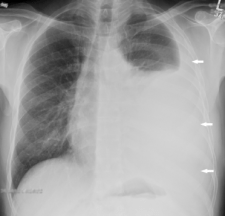

On my first day home of spring break, I entered an empty house. At that time, we had no cell phones, so I called a neighbour who told me that my parents went to the hospital. I Screen Shot 2017-06-18 at 10.00.09 PMimmediately called my brother and we went to see what was going on. My father had been suffering from a “cold” for a while and finally had broken down and gone to see the GP. The doctor ordered x-rays, one look told him something was very wrong. He told my parents to go emergency immediately, they did. A week later we were told he has terminal mesothelioma. The months that followed were fraught with joy, sadness and every emotion in between. I decided it would be best to come home and be with my family, a decision that I am so glad I made. We often wonder what could have been instead of what is, I have too. I regret nothing,